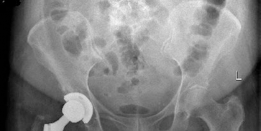

- This final image likely represents a post-operative radiograph of a successfully implanted uncemented acetabular component, demonstrating good position and fixation.

Clinical & Radiographic Imaging